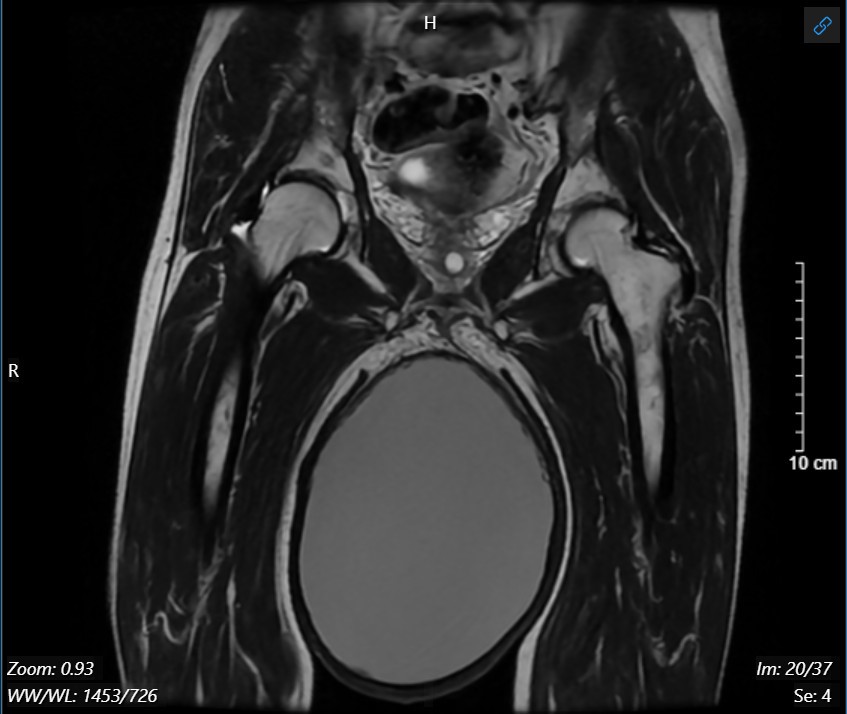

Phim chụp cộng hưởng từ khối u tinh hoàn phải

Bệnh nhân L.Đ.C (65 tuổi, trú tại Thanh Hóa ) phát hiện cơ thể có biểu hiện bất thường, kích thước tinh hoàn phải tăng dần từ khoảng 10 năm nay. Tuy nhiên, do không thấy đau và tinh hoàn to lên chậm nên bệnh nhân e ngại không đi khám. Chỉ đến thời gian gần đây, khi tinh hoàn trở lên rất lớn, gây khó khăn khi đi lại hoặc lúc tiểu tiện, bệnh nhân mới quyết định đến Bệnh viện Đại học Y Hà Nội kiểm tra. Qua thăm khám, các bác sĩ khoa Nam học và Y học giới tính, Bệnh viện Đại học Y Hà Nội phát hiện người bệnh có một khối u tinh hoàn bên phải kích thước khổng lồ hơn 20cm, ấn mềm. Kết hợp với các xét nghiệm và phương tiện chẩn đoán hình ảnh (siêu âm, chụp cộng hưởng từ), bệnh nhân được chẩn đoán U tinh hoàn phải, có chỉ định phẫu thuật cắt bỏ khối u.

Do kích thước lớn, thời gian khởi phát đã lâu nên phần lớn khối u dính rất nhiều vào các tổ chức xung quanh gây khó khăn cho cuộc mổ. Sau hơn 2 giờ phẫu thuật, khối u tinh hoàn đã được ekip mổ cẩn trọng bóc tách lấy ra ngoài thành công. Khối u nặng tới 2,5 kg, đường kính hơn 20cm, bên trong chứa gần 2000mL dịch đặc. Sau mổ, bệnh nhân sức khỏe ổn định, được chuyển về khoa Nam học và Y học giới tính để theo dõi và điều trị tiếp.